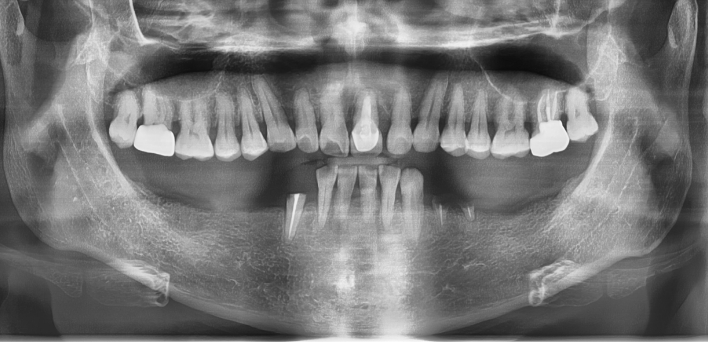

임플란트 케이스

임플란트 Before & After

The seoul dental clinic

치료 기록 더보기버튼

※ 더서울치과의원은 의료법을 준수하며 위 케이스는 실제 환자의 동의를 얻은 사례로 치료 전, 후가 동일한 환경에서 촬영되었습니다.

환자 케이스에 따라 부작용이 발생할 수 있습니다. 이 부분은 의료진의 충분한 상담과 체크를 통해 예방하고 줄일 수 있습니다.

[임플란트 부작용] 수술 후 관리가 소홀할 경우 출혈, 주위염 등의 부작용이 발생할 수 있어 구강 위생을 철저히 유지하고, 정기적인 검진을 통해 상태를 점검하는 것이 중요합니다.